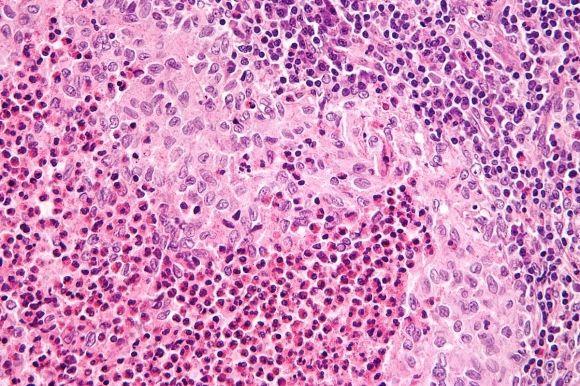

В хвосте поджелудочной железы человека, словно островки в океане, разбросаны крошечные скопления особых клеток. Эти скопления и выглядят как островки, и названы так — островки Лангерганса, по имени берлинского врача, рассмотревшего их под микроскопом полтора века назад. По слогам: Лан-гер-гáнс.

Общая масса островков Лангерганса — около грамма, но это важнейший эндокринный орган, секретирующий пять жизненно необходимых гормонов, среди которых — инсулин. Insula, в переводе с латыни, означает «остров»; молекулы инсулина можно вообразить как островитян с тех самых островков Лангерганса.

Почему же гибнут инсулоциты (β-клетки) в островках Лангерганса? Их, «сойдя с ума», атакует иммунная система. С высокой вероятностью, триггерами этого сбоя, на фоне генетической предрасположенности, являются факторы окружающей среды: вирусы, токсины. Отмечена статистическая связь T1D с питанием грудных детей продуктами из коровьего молока.